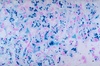

Describe the process occuring

Fatty infiltration of the muscle fascicle